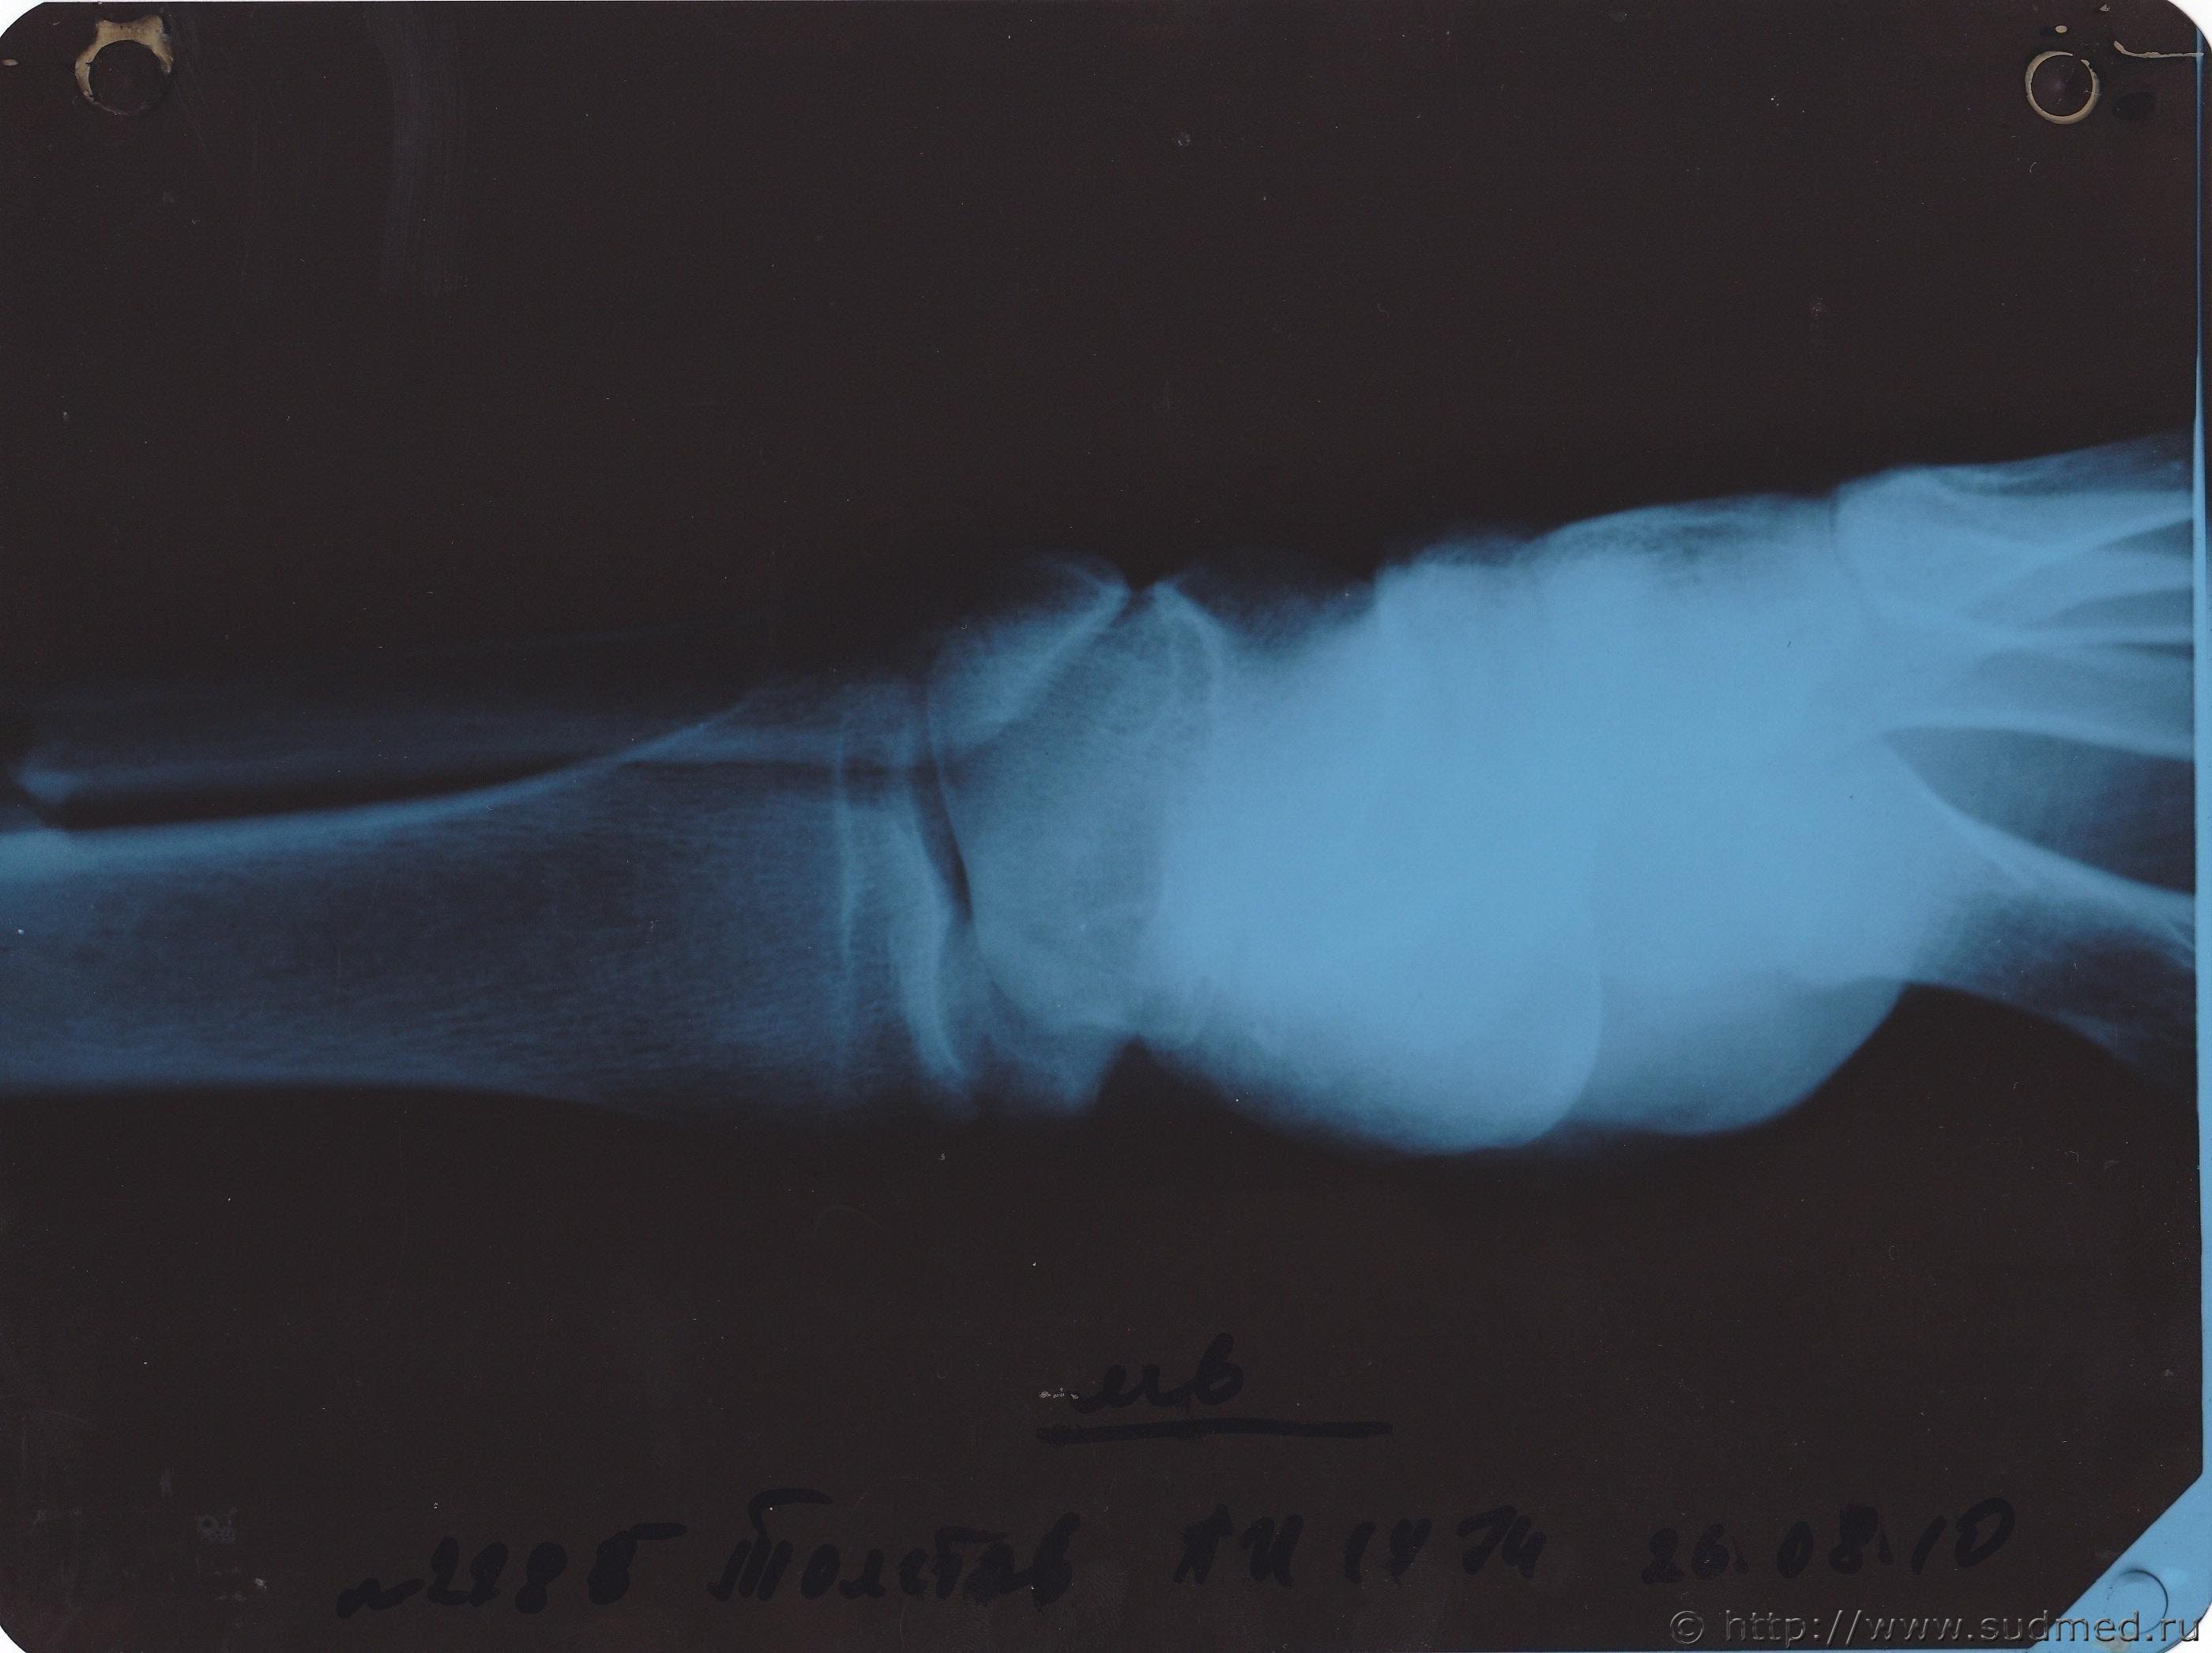

скажите по снимку можно судить о степени тяжести травмы

Gladius а что за снимок? при чем он вообще к переломам гол... 1.10.2010 - 01:21